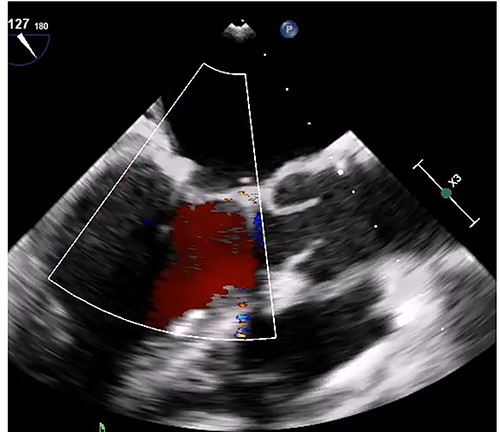

Median sternotomy was performed, and cardiopulmonary bypass was established via aortic and bicaval cannulation. Under cardiac arrest with antegrade cardioplegia perfusion, the LA was examined via the transseptal approach. The LA cavity was filled with the mass that the stalk was attached to the septal wall at the LA side, and the mass was too big and resected in pieces (Fig. 2). The mitral valve leaflet was intact, and the atrial septum was closed. Dilatated tricuspid annulus was fixed using a flexible band (Tailor Flexible band 29 mm, Abbott). After unclamping of the ascending aorta, a transesophageal echocardiogram points out moderate mitral regurgitation due to mitral annulus dilatation (Fig. 3). Cardiac arrest was performed again, and mitral annuloplasty was performed with a semi-rigid ring (Carpentier-Edwards Physio Ring II 26 mm, Edwards) via left atriotomy. His heart sinus rhythm returned to normal with successful weaning from cardiopulmonary bypass. After the transesophageal echocardiogram procedure, no evidence of the mass and residual mitral regurgitation was confirmed (Fig. 4).

Intraoperative transesophageal echocardiogram after the myxoma resection. Moderate mitral regurgitation with annulus dilatation was detected.